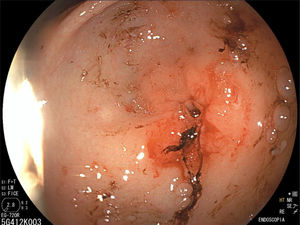

The endoscopy revealed a narrowing of the pylorus that prevented the endoscope from entering the duodenum (Fig. 1), leading to performance of hydrostatic balloon dilation (Figs. 2 and 3). The analysis of the biopsy specimens led to diagnosis of gastritis associated with Helicobacter pylori infection and foveolar hyperplasia.